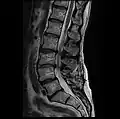

MRI lumbar spine with degeneration, post-hemilaminectomy L4-5 (sagittal T2 FRFSE)

MRI lumbar spine with degeneration, post-hemilaminectomy L4-5 (sagittal T1 FSE)

MRI lumbar spine with degeneration, post-hemilaminectomy L4-5 (sagittal FAST STIR)- MRI lumbar spine post-hemilaminectomy (sagittal T2 FRFSE)